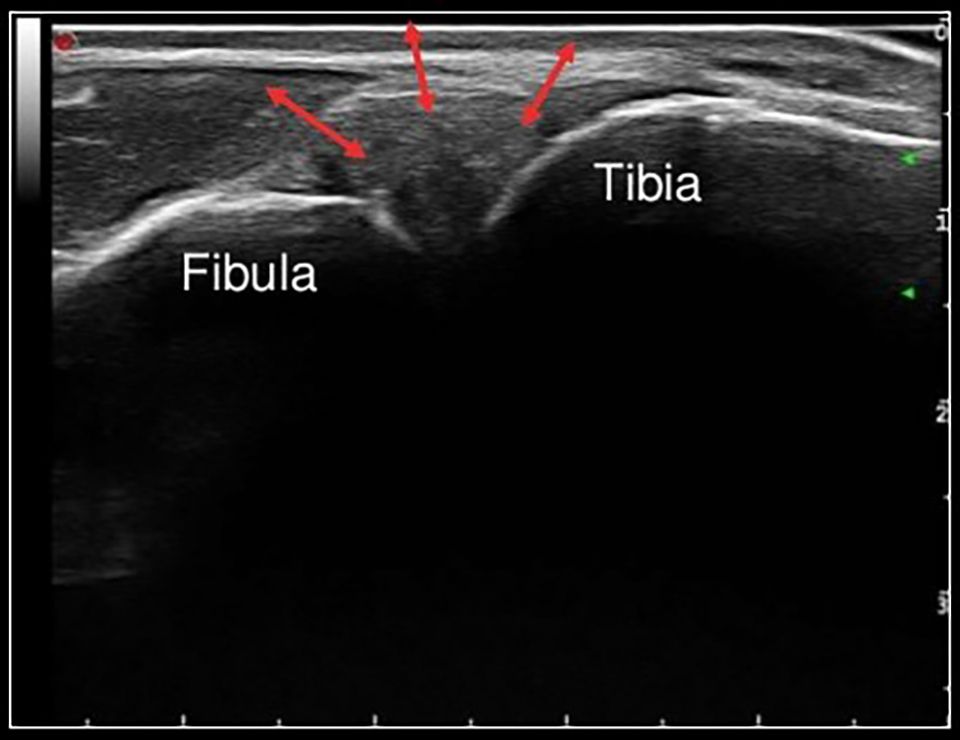

Ultrasound (Figure 12)

Side to side difference of tibiofibular clear space can be evaluated with ultrasound. Differences were less than 1mm in all positions with high ICC values between ankles in one study. [31] The authors conclude that by using 3D-US, they were able to consistently evaluate the clear space with good reliability. One other study reported a sensitivity of 0.89 and specificity of 0.97 for diagnosing syndesmotic insufficiency. [32]